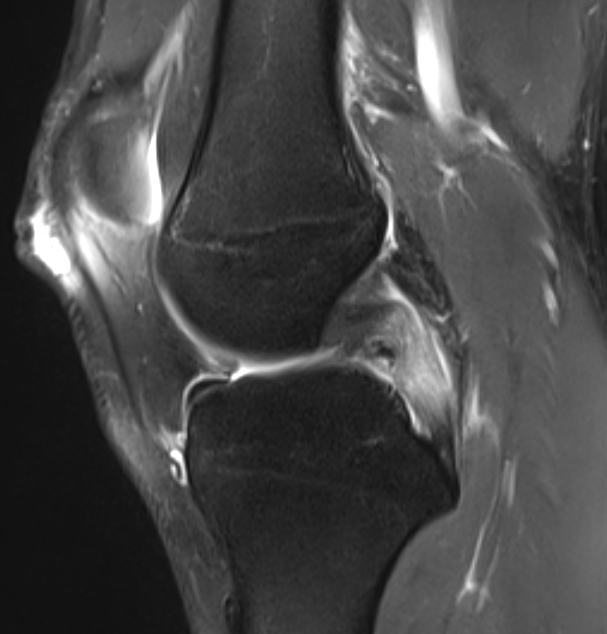

3. Posterior Cruciate Ligament Tear